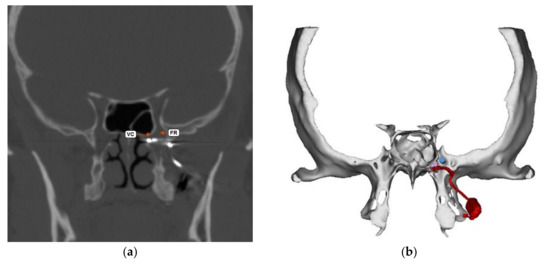

The Pathway CH-2 clinical trial “Sphenopalatine Ganglion Stimulation for Treatment of Chronic Cluster Headache” was an FDA approved study sponsored by Autonomic Technologies, Inc. (ATI), commencing in 2014. It was a multi-center, interventional, randomized, placebo-controlled, parallel, triple-blind safety and efficacy study that included intra-operative procedures for the implantation of the ATI-Neurostimulator in the pterygopalatine fossa so that an active electrode was within 0.5 mm of the sphenopalatine ganglion to intercept cluster headache symptoms at the onset. Each patient signed informed consent approved by the UTSW IRB committee (STU#052015-044). The results of this clinical trial have been previously published [16]. The sphenopalatine ganglion is located at the terminal end of the vidian canal, which contains the greater and lesser petrosal nerves that are preganglionic parasympathetic afferents synapsing in the sphenopalatine ganglion, which are shown to be involved in inducing the trigeminal autonomic reflex onset of cluster headaches [17]. Thus, stimulating the sphenopalatine ganglion would intercept this interaction and terminate the cluster headache. Figure 1 shows a coronal CT scan and adjacent illustration showing the position of the vidian canal (VC) in the medial portion of the pterygopalatine fossa. Just lateral to the VC is the foramen rotundum (FR), which contains the main trunk of the trigeminal maxillary division (V2). The CT view shows visible electrodes properly positioned to stimulate the sphenopalatine ganglion, and the illustration shows the trajectory of the implant close to FR and the transmitter connection on the lateral maxilla. Implantation of the ATI-Neurostimulator is performed through a small surgical incision through the maxillary posterior mucosa to expose the base of the zygoma and the pterygomaxillary plate. An introducer is used to position the implant at the sphenopalatine ganglion site under fluoroscopy. Figure 2 shows an illustration of the introducer device used to position the ATI-Neurostimulator. The electrodes are inactive during placement and only stimulated after the implant has been fixated. The TCR events precede activation, thus, the proposed mechanism of TCR induction is a mechanical interaction with V2 near the FR during use of the introducer device and subsequent positioning of the implant for fixation. Figure 3 shows a lateral CT view of an ATI-Neurostimulator after fixation.

Figure 1. Coronal CT and illustration of the ATI-Neurostimulator in the pterygopalatine fossa with the terminal electrode within 0.5 mm of the sphenopalatine ganglion at the vidian canal (VC). The location of the foramen rotundum (FR) is shown in close proximity and lateral to the VC. (a) Shows CT image and terminal electrodes in proper position. (b) Shows illustration of A showing the position of the electrodes and the stimulators components on the lateral posterior maxilla.

Figure 2. An illustration showing the trajectory of the implant introducer device used to place the ATI-Neurostimulator at the location of the sphenopalatine ganglion in the pterygopalatine fossa from an intra-oral incision at the posterior superior vestibule of the maxilla.